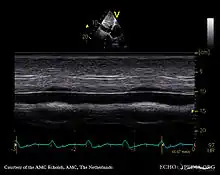

Echocardiography

If pulmonary hypertension is suspected based on the above assessments, echocardiography is performed as the next step.[12][15][58] A meta-analysis of Doppler echocardiography for predicting the results of right heart catheterization reported a sensitivity and specificity of 88% and 56%, respectively.[60] Thus, Doppler echocardiography can suggest the presence of pulmonary hypertension, but right heart catheterization (described below) remains the gold standard for diagnosis of PAH.[12][15] Echocardiography can also help to detect congenital heart disease as a cause of pulmonary hypertension.[12]